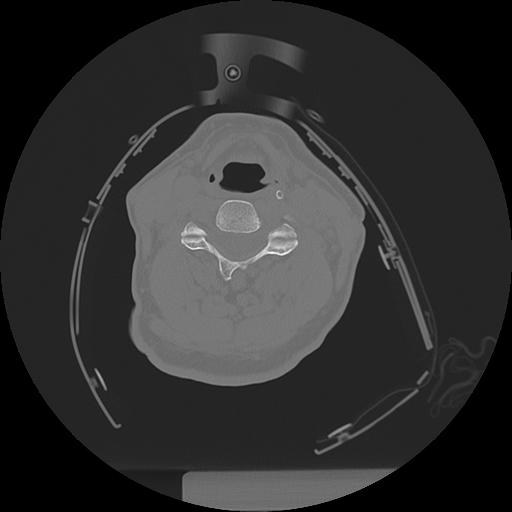

11 HUESO,,Axial,2.0,HUESO,,